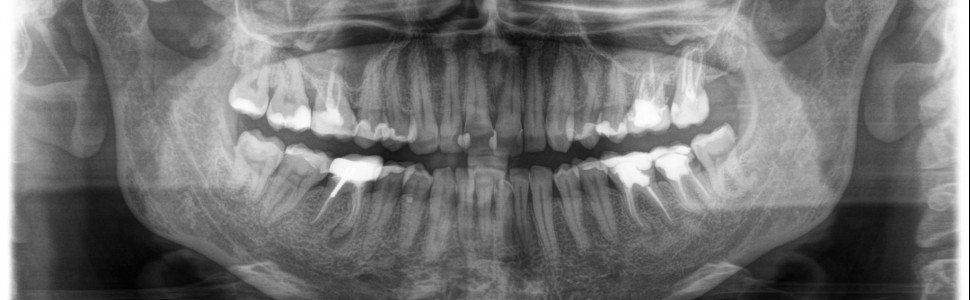

Artykuł opisuje ponowne leczenie endodontyczne pierwszego zęba trzonowego żuchwy po stronie lewej. Podczas leczenia zlokalizowano via falsa w kanale korzeniowym, odnaleziono prawidłowy przebieg kanału korzeniowego, złamano pilnik endodontyczny i ostatecznie kanały wypełniono metodą kondensacji pionowej ciepłej gutaperki.

The article describes endodontic retreatment of the mandibular first molar on the left side. Via falsa was located during treatment in the root canal, next the correct course of the root canal was found, in the next part an endodontic file was broken, finally the root canals were filled by warm guttapercha vertical condensation method.